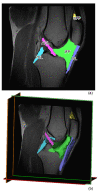

Several studies have investigated cartilage degeneration and inflammatory subchondral bone and synovial membrane changes using magnetic resonance (MR) in osteoarthritis (OA) patients. Conversely, there is a paucity of data exploring the role of knee ligaments, infrapatellar fat pad (IFP), and suprapatellar fat pad (SFP) in knee OA compared to post-traumatic cohorts of patients. Therefore, the aim of this study was to analyze the volumetric and morphometric characteristics of the following joint tissues: IFP (volume, surface, depth, femoral and tibial arch lengths), SFP (volume, surface, oblique, antero−posterior, and cranio−caudal lengths), anterior (ACL) and posterior cruciate ligament (PCL) (volume, surface, and length), and patellar ligament (PL) (volume, surface, arc, depth, and length). Eighty-nine MR images were collected in the following three groups: (a) 32 patients with meniscal tears, (b) 29 patients with ACL rupture (ACLR), and (c) 28 patients affected by end-stage OA. Volume, surface, and length of both ACL and PCL were determined in groups a and c. A statistical decrease of IFP volume, surface, depth, femoral and tibial arch lengths was found in end-stage OA compared to patients with meniscal tear (p = 0.002, p = 0.008, p < 0.0001, p = 0.028 and p < 0.001, respectively) and patients with ACLR (p < 0.0001, p < 0.0001, p = 0.008 and p = 0.011, respectively). An increment of volume and surface SFP was observed in group b compared to both groups a and c, while no differences were found in oblique, antero−posterior, and cranio−caudal lengths of SFP among the groups. No statistical differences were highlighted comparing volume, surface, arc, and length of PL between the groups, while PL depth was observed to be decreased in end-OA patients compared with meniscal tear patients (p = 0.023). No statistical differences were observed comparing ACL and PCL lengths between patients undergoing meniscectomy and TKR. Our study confirms that IFP MR morphometric characteristics are different between controls and OA, supporting an important role of IFP in OA pathology and progression in accordance with previously published studies. In addition, PL depth changes seem to be associated with OA pathology. Multivariate analysis confirmed that OA patients had a smaller IFP compared to patients with meniscal tears, confirming its involvement in OA.